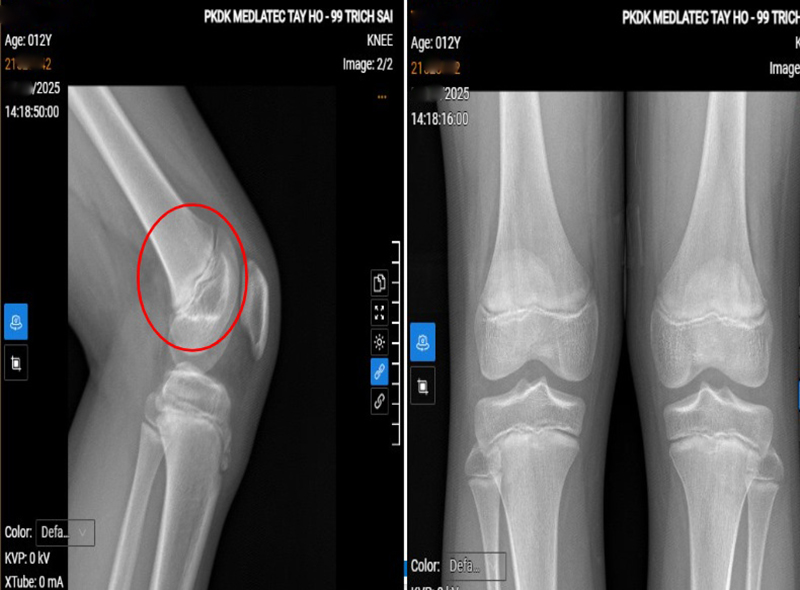

Phim chụp tổn thương của bệnh nhi.

Để xác định nguyên nhân, bác sỹ chỉ định siêu âm, X-quang và chụp MRI khớp gối. Kết quả siêu âm cho thấy phù nề nhẹ tại điểm bám gân bánh chè; X-quang ghi nhận hình ảnh theo dõi hoại tử vô khuẩn lồi củ xương chày; MRI phát hiện phù nhẹ dây chằng chéo trước, phù xương và mô mỡ quanh lồi củ chày, tất cả gợi ý bệnh cảnh viêm lồi củ trước xương chày.